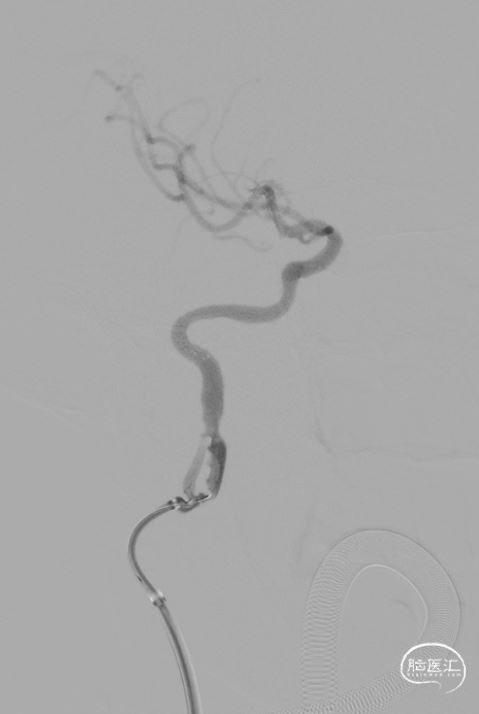

再次沿导丝送入Xpert Pro(6X40mm)支架,回撤长鞘,对位准确后成功释放支架,再次造影提示支架贴壁良好,前向血流通畅(TICI分级3级)。

观察十分钟后再次造影提示右侧颈内动脉全程血流通畅,无明显急性血管闭塞征象,前向血流3级。术中DynaCT未见明显造影剂渗出。撤出导引导管,拔除动脉鞘,使用雅培缝合器 ProGlide缝合伤口,伤口加压包扎,结束手术。